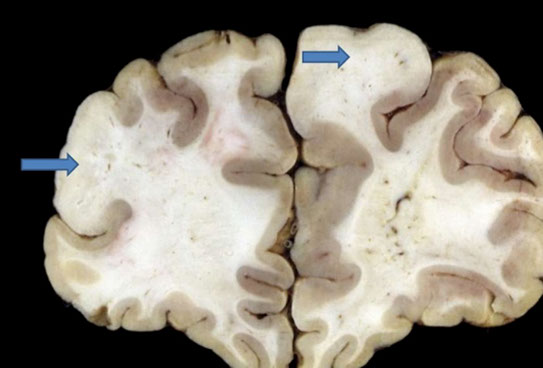

Huntington disease

- see atrophy of striatum (caudate nucleus and putament) ad frontal cortex

-- bc caudate borders lateral ventral ventricles, caudate atrophy causes hydrocephalus ex vacuo

Gross: atrophy of the caudate nucleus and putamen associated with a diffuse neuronal loss.

Sx Chorea, depression, progressive dementia

Dx: Atrophy of caudate nucleus and >40 CAG repeats